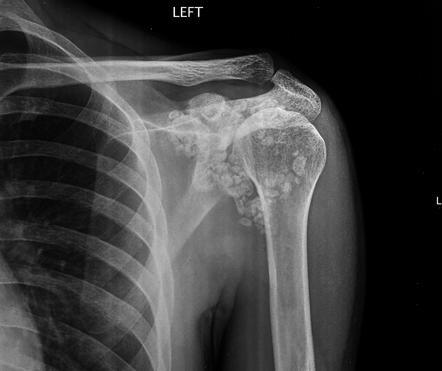

Synovial chondromatosis

synovial proliferation leading to multiple cartilaginous loose joint bodies–some ossify

1*– 4th-5th decades, M >F, unknown cause, Knee>Hip>elbow>shoulder

2*– to degenerative changes, fewer and larger fragments, older population, other degenerative findings\